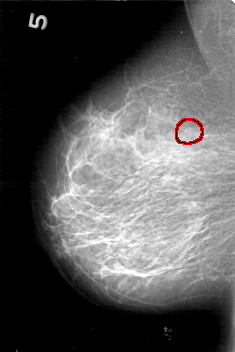

D_4167_1.RIGHT_CC

RIGHT_CC LINES 5206 PIXELS_PER_LINE 3766 BITS_PER_PIXEL 12 RESOLUTION 43.5 OVERLAY

FILE: D_4167_1.RIGHT_CC.OVERLAY

TOTAL_ABNORMALITIES 1

ABNORMALITY 1

LESION_TYPE CALCIFICATION TYPE PUNCTATE-AMORPHOUS DISTRIBUTION CLUSTERED

ASSESSMENT 0

SUBTLETY 2

PATHOLOGY BENIGN

TOTAL_OUTLINES 1

BOUNDARY